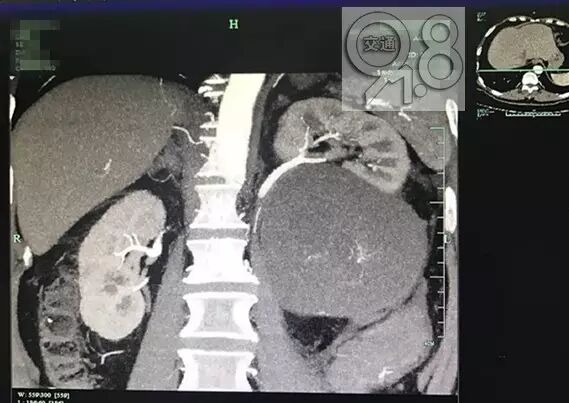

经过CT检查发现,大伯左侧长了一个腹膜后脂肪肉瘤。杭州市中医院泌尿外科黄亚胜副主任坦言:大伯的肿瘤长在左胃下方,有三四斤重,婴儿头那么大,选择手术治疗。这是生长到一定程度,才会出现的症状。切开这个肿瘤,发现里面都是些脂肪样的物质。”